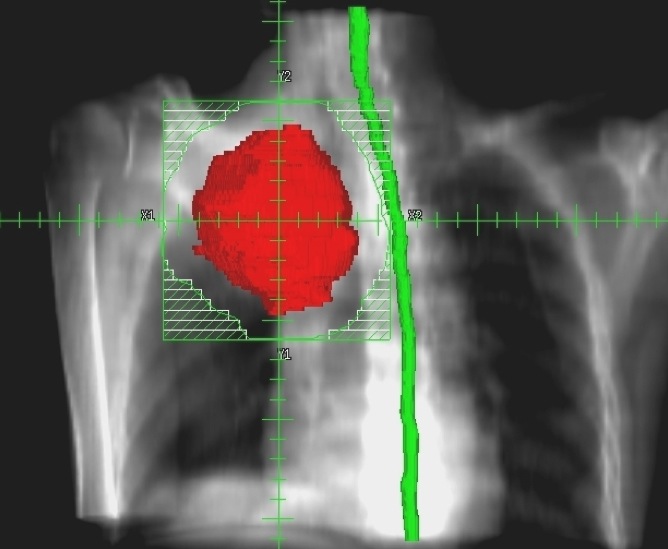

まず申し上げたいのは、最近の放射線治療は「がん」治療のかなでも副作用の少ない治療法とされています。それには多くの技術革新があっての結果ですが、一般にピンスポイント照射とも呼ばれている高精度な三次元治療計画が最も重要な役割を果たしています。それは副作用のでやすい臓器を避けて病巣に放射線を集中照射する技術です。写真4をご覧ください。

赤い肺癌に放射線照射を行うときに最も注意しなければならないのは緑の脊髄です。画像情報を駆使して、脊髄障害を起こさずに肺癌病巣に照射する方法を事前に十分検討してから、最も良い方法を選んで実際の治療を行うのです。写真5は主に食道に放射線を集中しものですが、ここでは前後にある心臓と脊髄を避けて4方向から照射しています。この方法で癌病巣や脊髄・心臓にどの位の放射線があたるのかを写真6のようなグラフを描いて評価します。したがって、昔のコバルト治療時代の副作用とは比較にならないほど軽く済むことが多くなりました。それでも副作用には個人差があり、特に治療中に発生する早期反応は化学療法でも強まり、ある程度は我慢しなければならない場合もあるでしょう。さらに副作用に対応する腫瘍看護学も進歩しており、日常のケアが行き届くようになっていますので、何か辛いことがあれば医療スタッフに遠慮なく相談したほうがよいでしょう。